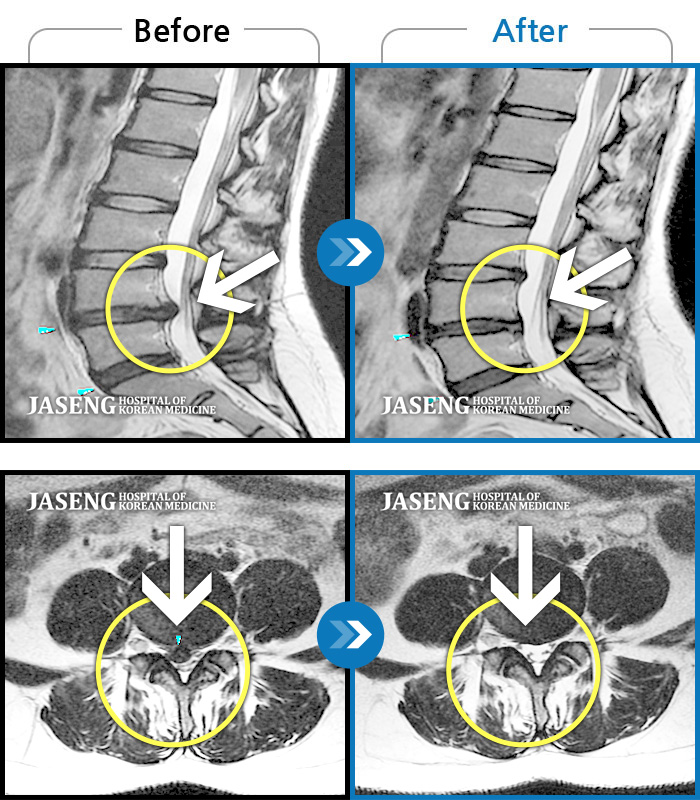

Before

After

환자에게 사전 동의를 받아 동일 조건에서 촬영되었습니다.

개인에 따라 치료 후 부작용이 발생할 수 있으니 의료진과 상담 후 치료를 진행하시기 바랍니다.

허리 통증 및 좌하지 방사통

허리 골반통증 및 우하지 방사통, 감각저하